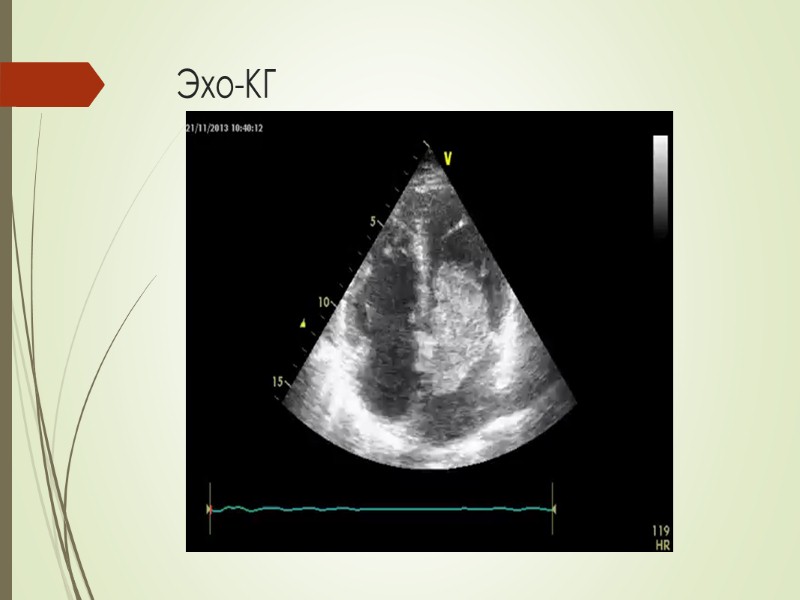

Диагностика Эхо-КГ (трансторакальная и чрезпищеводная)

Эхо-КГ